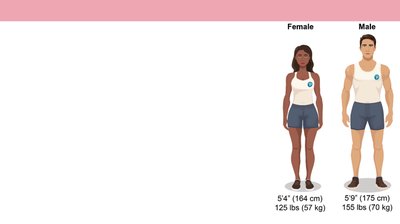

There is significant variation in human anatomy and physiology. Textbooks use a 'reference body' (healthy young adult, average size) for consistency, but real individuals may differ.

Reference Body: Female: 5'4" (164 cm), 125 lbs (57 kg); Male: 5'9" (175 cm), 155 lbs (70 kg).

Anatomical Variation: Common in blood vessels, organs, and other structures.

Example: There are multiple common variants in the branching of blood vessels to the liver and gallbladder.